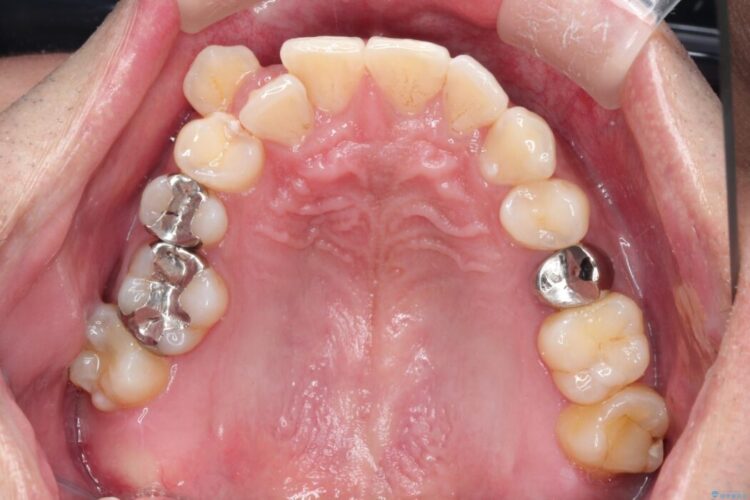

右上の八重歯と、下の歯の凸凹を治したいとご来院されました。

上顎右側第一小臼歯と下顎右側第一小臼歯を抜歯しワイヤー矯正を行いました。

噛み合わせのズレが右側で大きかった(2級)ため、右側上下2本の歯を抜歯し、ワイヤー矯正で噛み合わせを左右対称の理想的な位置に改善しました。